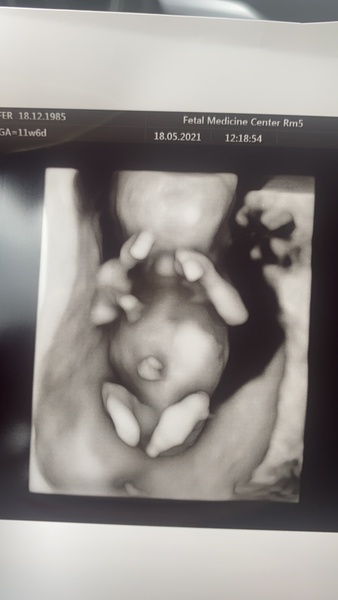

jdr1234 · 18/05/2021 15:03

Afternoon all, scan went well. Lovely little baby moving around in there. Results all came back low risk and due date is 29th November. Wishing all the best for those waiting for 12 weeks, it felt like an eternity so hoping the next trimester goes a bit quicker!

Horehound · 18/05/2021 17:16

Great scan @jdr1234! Did you pay for that to be 3D?

jdr1234 · 18/05/2021 17:29

@Horehound it was a private scan as part of a harmony package so they did those and regular 2d ones as standard. My nhs scan isn’t till next Monday.